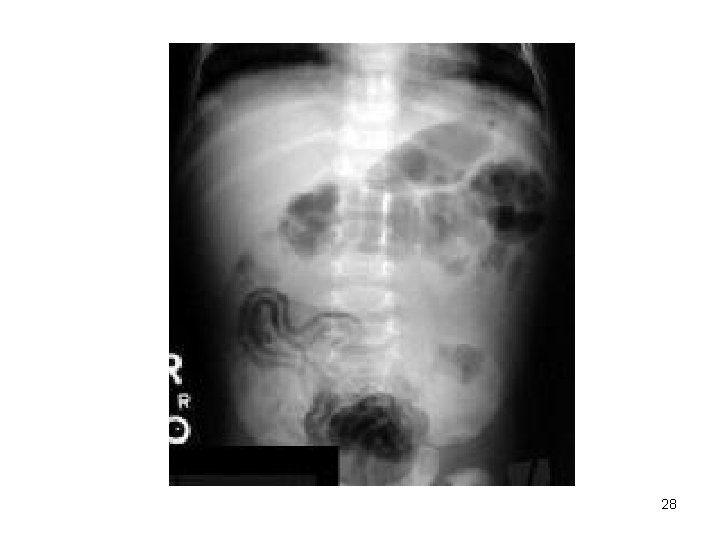

TANI Sepsis Bulguları: Lökositoz/nötropeni; >CRP; Trombositopeni; Kan gazı boz. ; elektrolit dengesizliği. . . RADYOLOJİ** Abdominal X-Ray Abdominal MRI; USG 26

27

28